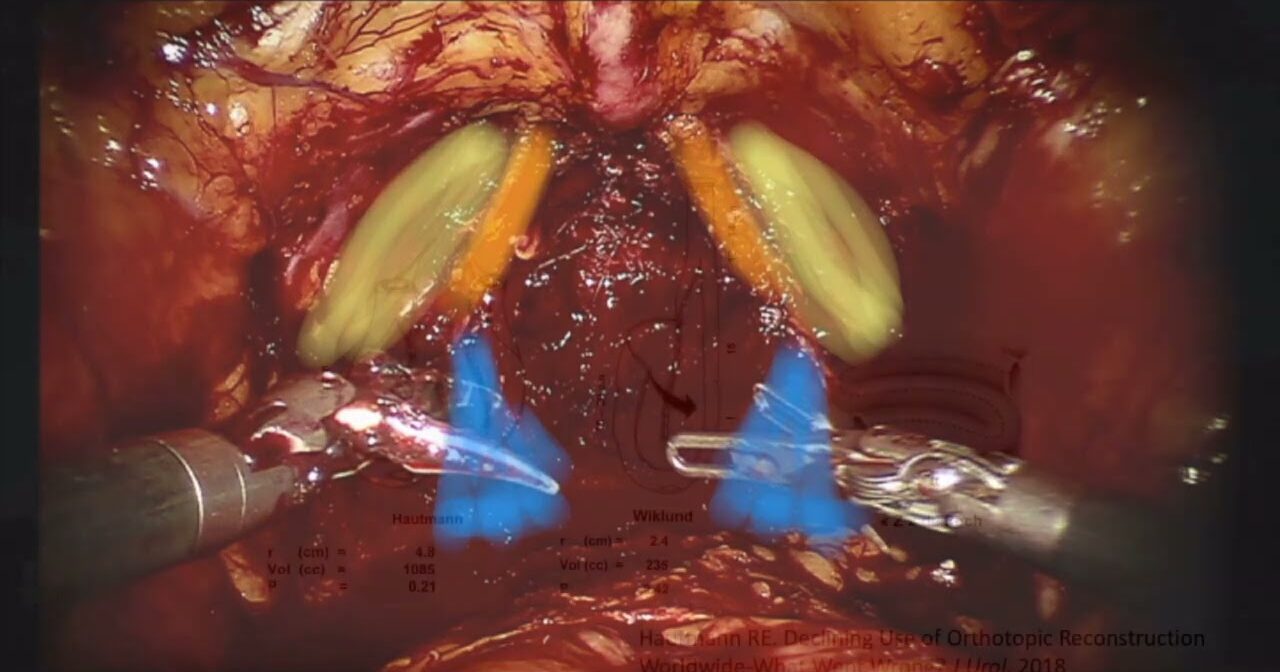

RARC and intracorporeal orthotopic neobladder

Robotics, Urology ';